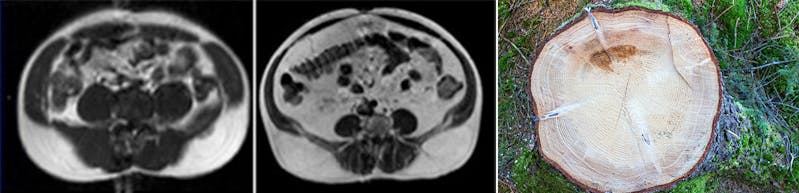

These are scans of two patients with the same waist circumference. To understand what you are looking at, imagine looking at all the circles inside a sawn tree.

On the left, you see a fair amount of muscles. It’s the black oval shapes you see right underneath the white outer layer of fat.

On the right, you can see a very thin layer of muscles under the fat. You can also see a LOT of white fat inside the abdominal cavity. It’s all around and inside the organs. We call these people TOFI, which means thin on the outside and fat on the inside. A TOFI can look normal or healthy, but that is deceiving.